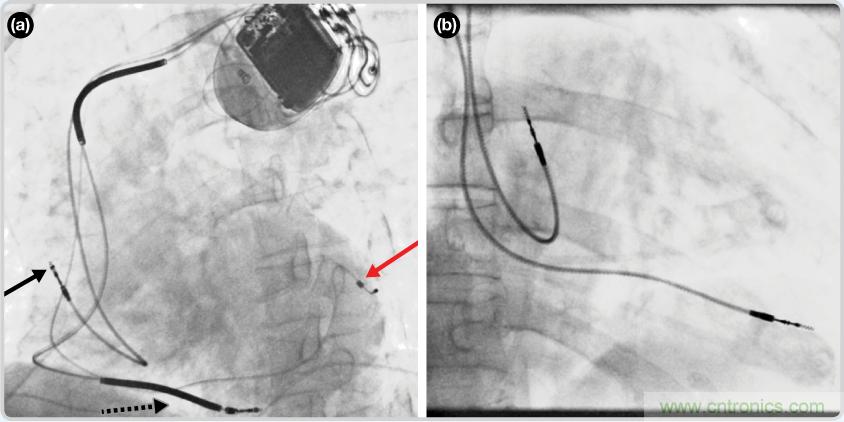

CRT器件在圖4(a)中的透視圖像中可以看見(jiàn)。醫(yī)師就是利用這種影像來(lái)放置導(dǎo)聯(lián)線的。對(duì)于非專業(yè)人士來(lái)說(shuō),這種影像是很難解讀的??梢钥吹叫呐K淡淡的輪廓——這是搏動(dòng)中的心臟的靜態(tài)視圖。起搏器位于右心房上,心臟頂點(diǎn)指向右下方。在這個(gè)典型的導(dǎo)聯(lián)線放置實(shí)例中,黑色箭頭指向右心房導(dǎo)聯(lián)線。虛線黑色箭頭指向右心室導(dǎo)聯(lián)線。紅色箭頭標(biāo)示的導(dǎo)聯(lián)線只能看到一部分,這是左心室導(dǎo)聯(lián)線(紅箭頭指向電極尖端)。圖4(b)展示的是雙腔起搏器的典型導(dǎo)聯(lián)線放置透視圖像。右心房導(dǎo)聯(lián)線指向上方,置于右心房中。右心室導(dǎo)聯(lián)線則位于右心室頂部。

圖4. 起搏器導(dǎo)聯(lián)線放置的透視圖像3 (a). 單腔起搏器;(b).雙腔起搏器